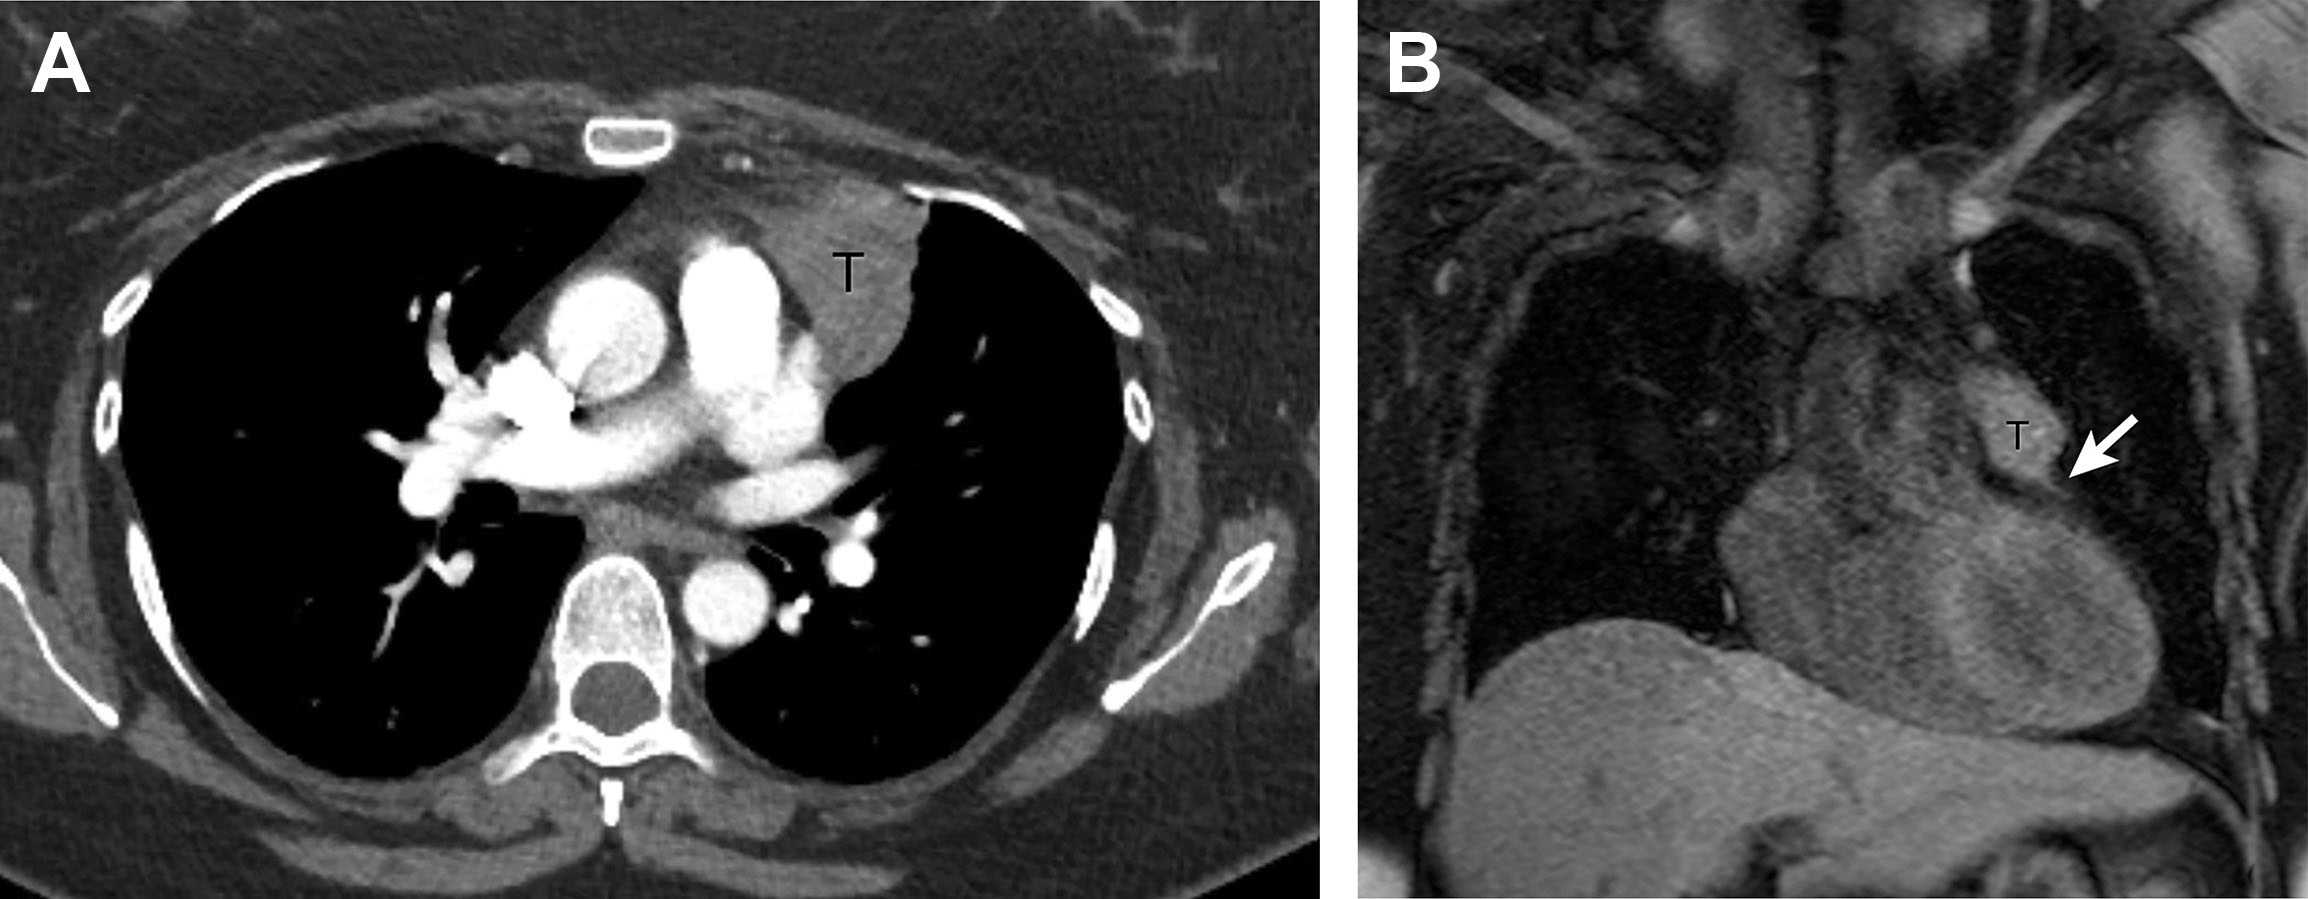

Diagnosis of rebound thymic hyperplasia (RTH), (A) computed tomography Thymic Rebound Radiology Find out how to distinguish it. Rebound thymic hyperplasia (rth) is a common phenomenon caused by stress factors such as chemotherapy (ctx) or radiotherapy, with an incidence between 44% and. The purpose of this article is to investigate the imaging characteristics of pathologically proven thymic hyperplasia and to identify features that can differentiate true hyperplasia from lymphoid hyperplasia. Learn about. Thymic Rebound Radiology.